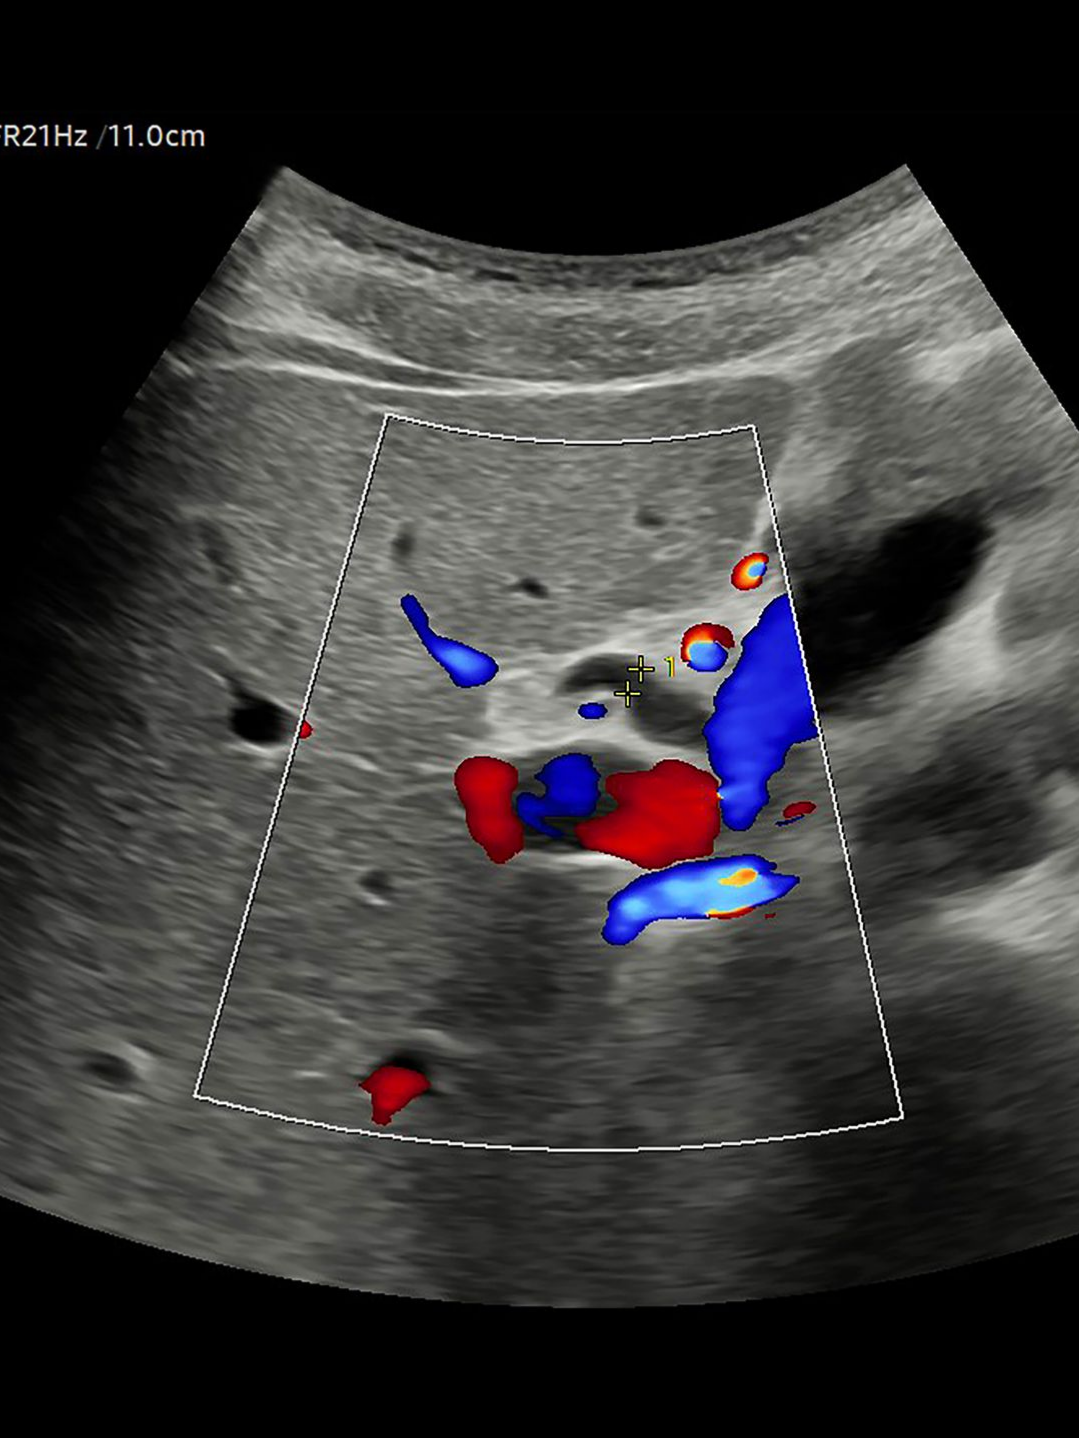

L’échographie abdominale est un examen d’imagerie médicale qui utilise les ultrasons pour visualiser les organes, tels que le foie, la vésicule biliaire, les reins, le pancréas, la rate ou encore la vessie.

Le patient est allongé sur le dos et un gel est appliqué sur l’abdomen pour permettre une bonne conduction des ultrasons. Le radiologue déplace une sonde sur différentes zones de l’abdomen afin d’obtenir des images en temps réel du foie, de la vésicule biliaire, des reins, du pancréas, de la rate, la vessie et parfois des intestins pour l'appendicite.

Le médecin s’attend à confirmer ou écarter d’éventuelles anomalies telles que des calculs, des kystes, des masses, des inflammations ou des signes d’infection.